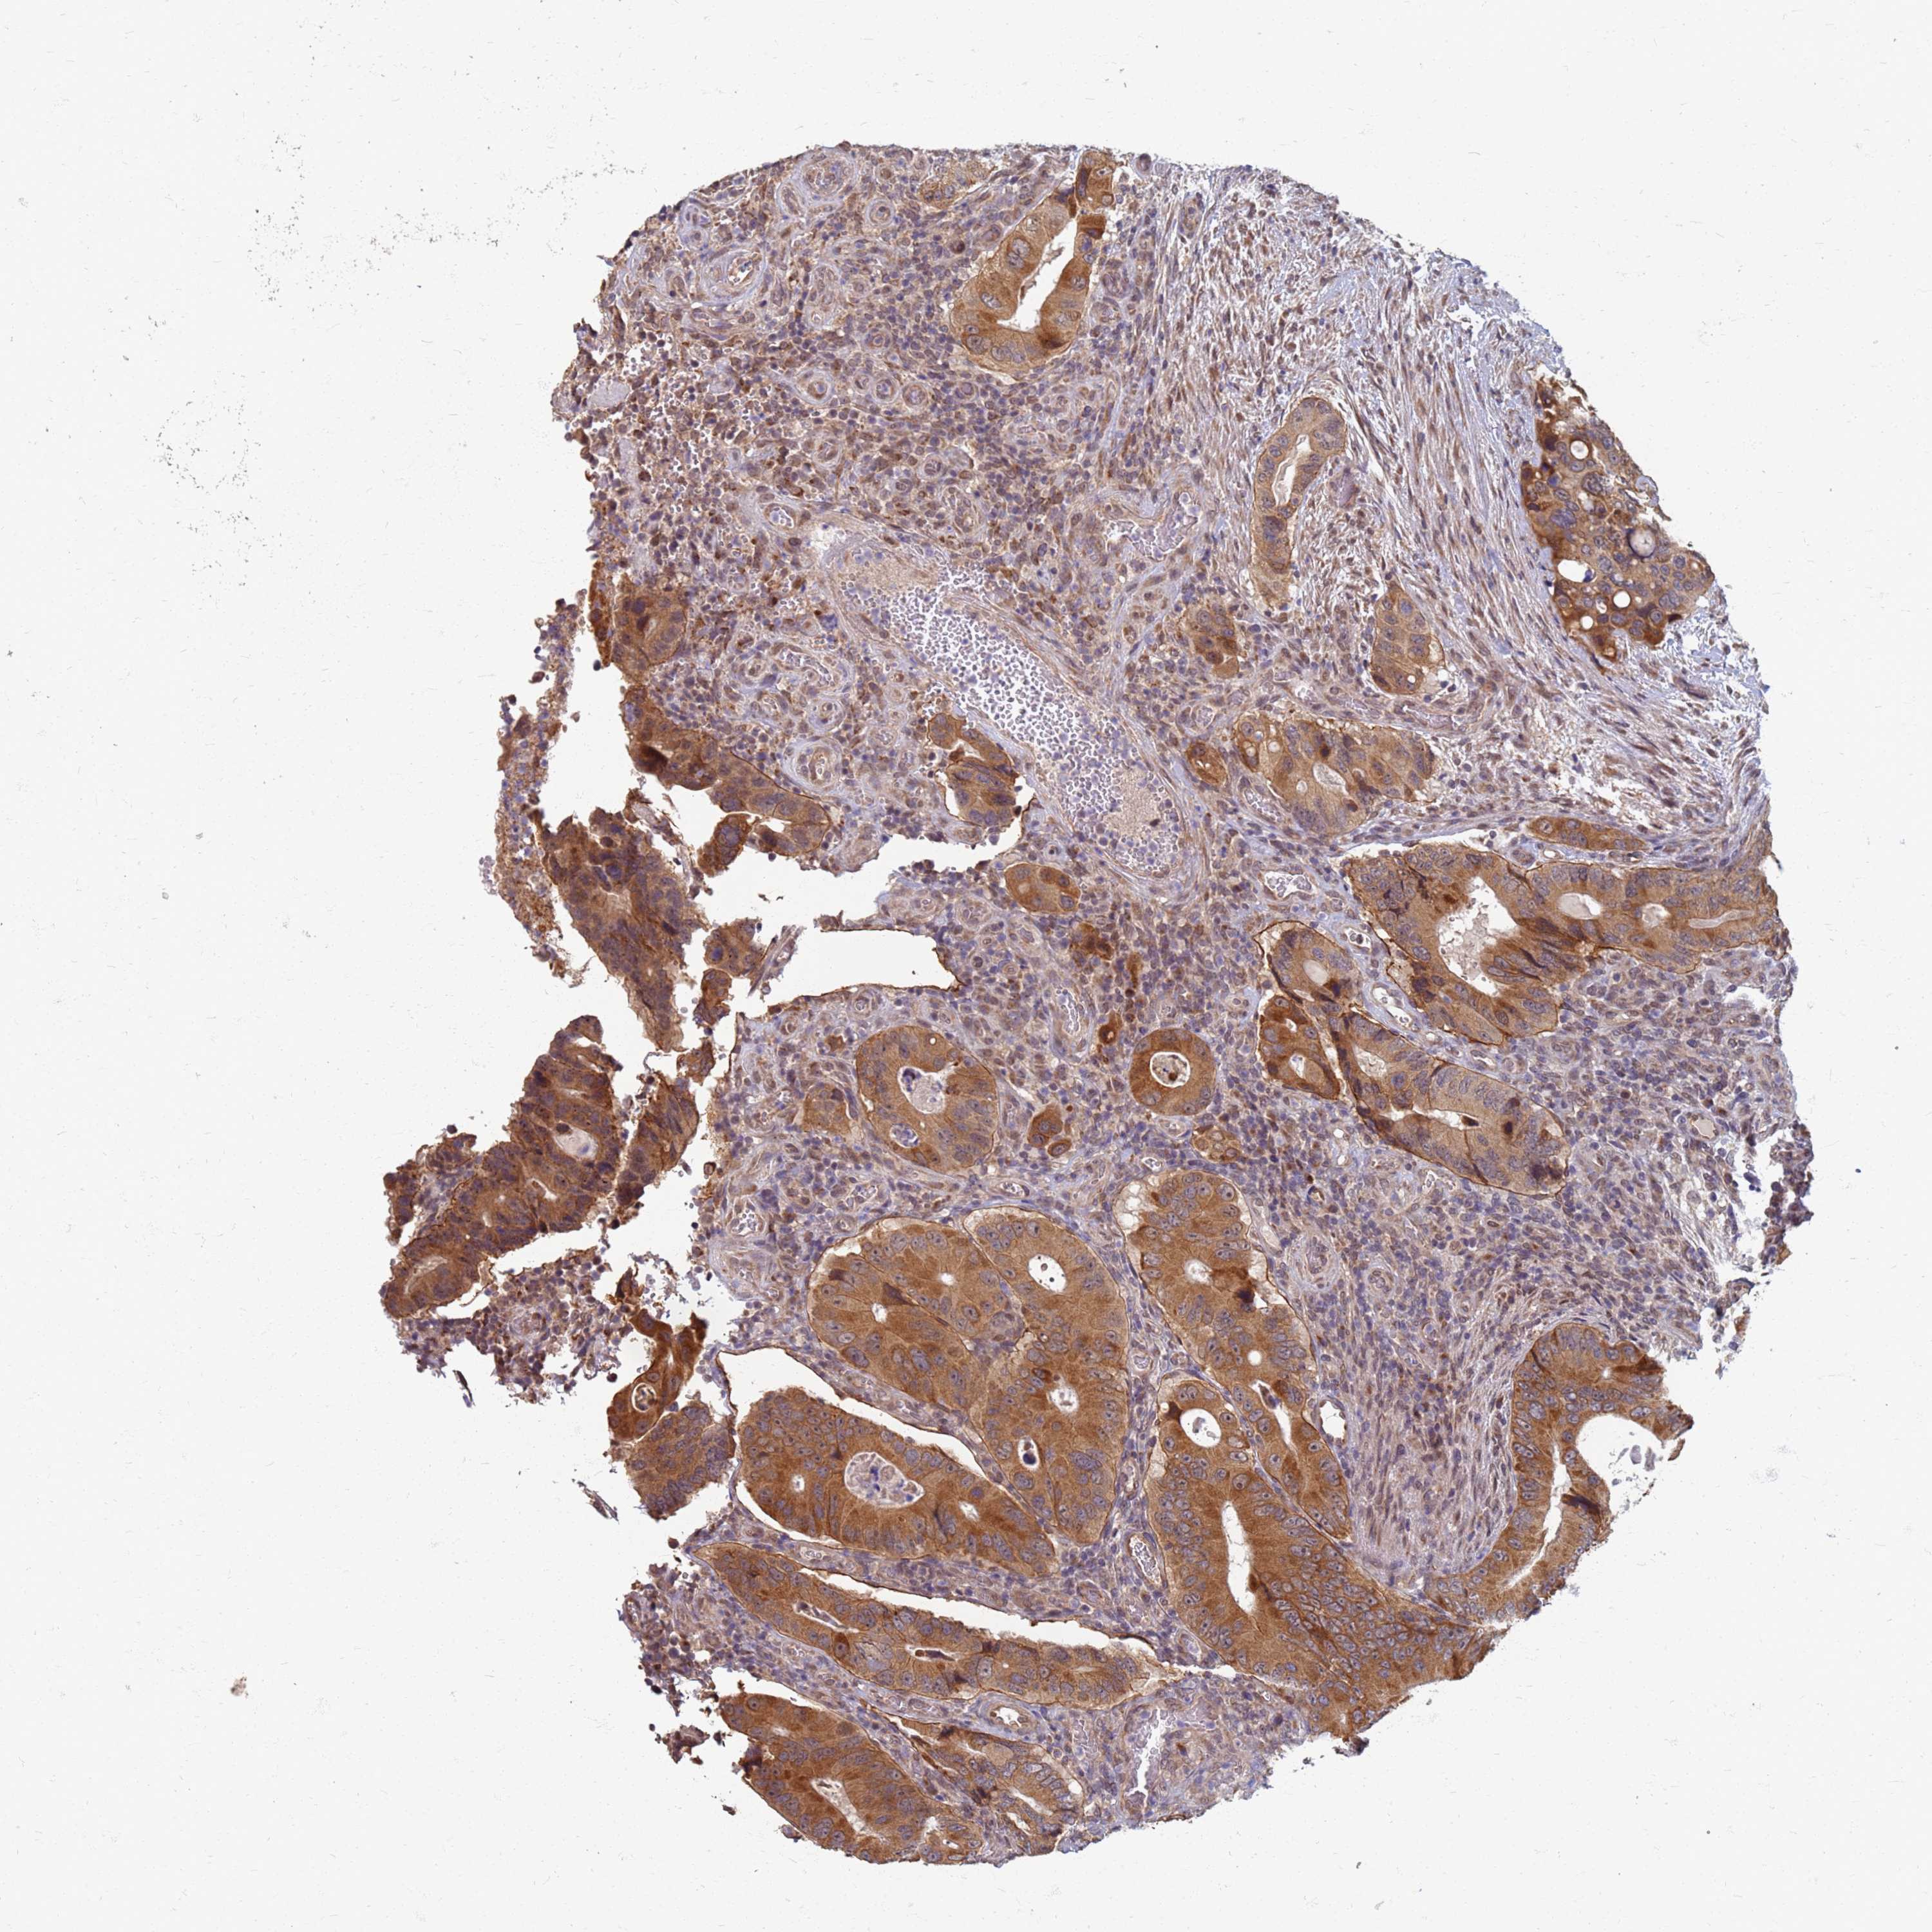

CANCER COLORECTAL CANCER Show tissue menu

Colorectal cancer

Human cancer

Colon adenocarcinoma